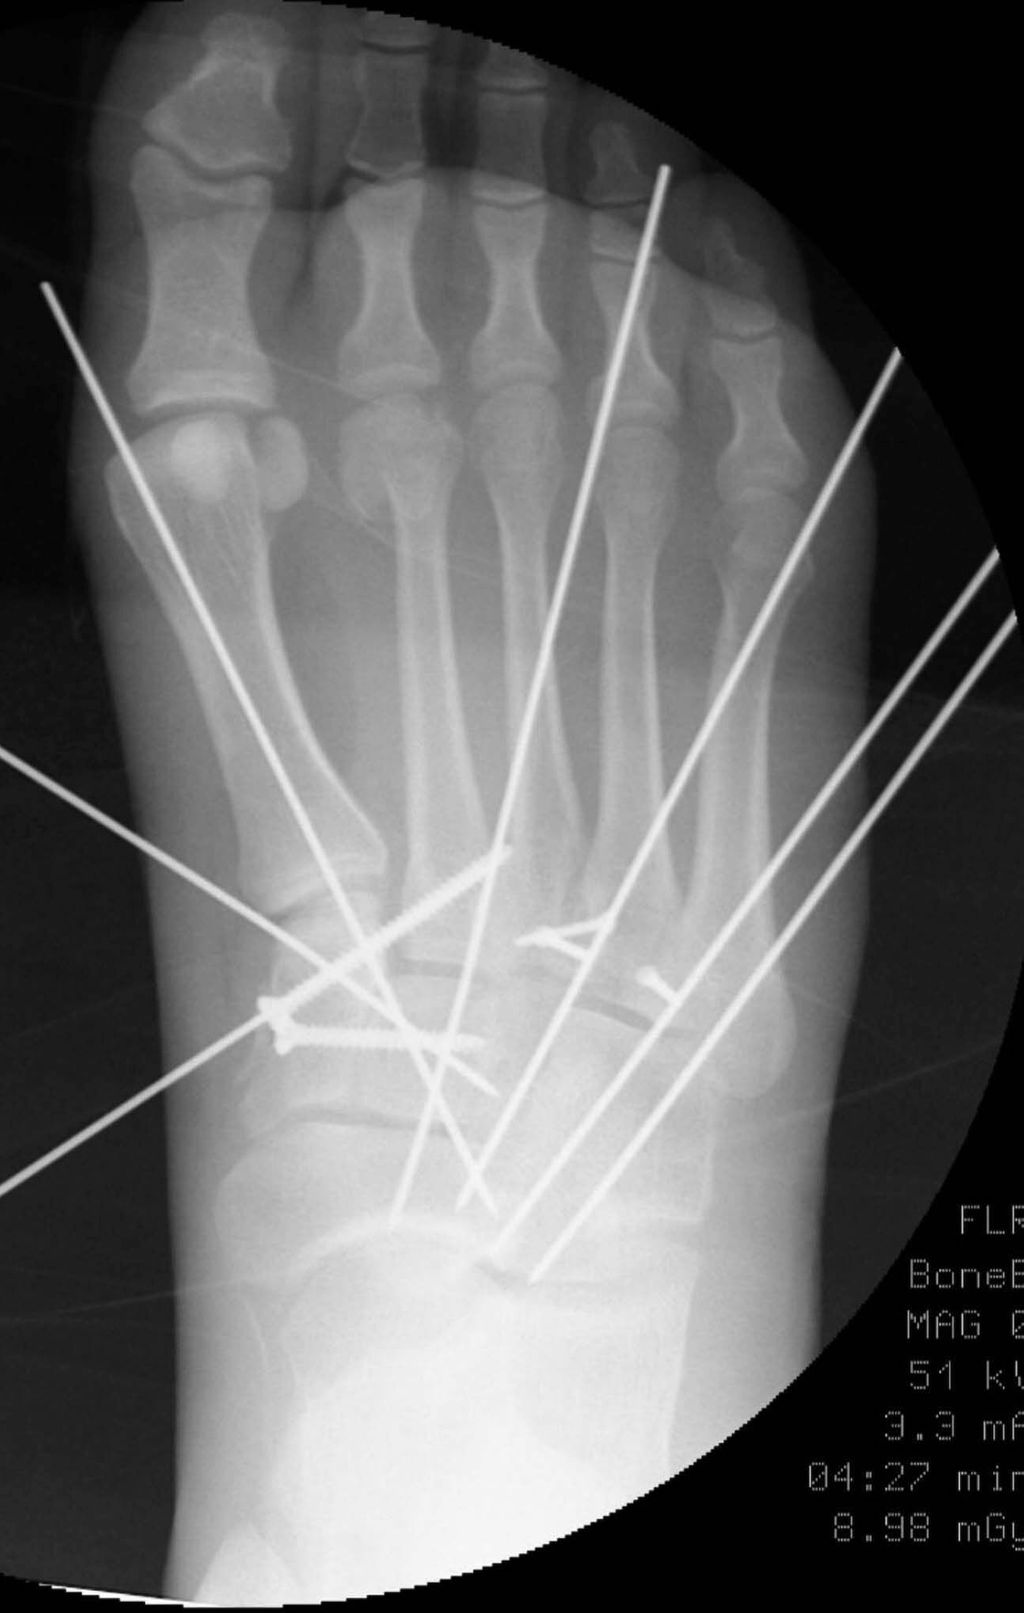

Die Reposition der Lisfranc-Luxation beginnt am zweiten Tarsometatarsalgelenk, welches in seiner anatomischen Form zwischen Os cuneiforme mediale und intermedium als auch an der Basis des Os metatarsale III geführt wird. Hierbei ist auch der Abstand zwischen Os cuneiforme mediale und dem Os metatarsale II wiederherzustellen, wobei eine Repositionszange in Zugrichtung des „Lisfranc-Ligaments“ aufgesetzt wird (Abb. 4). Anschließend werden nun der erste und der dritte Strahl reponiert und mit Kirschnerdrähten fixiert (Abb. 5).

Nun erfolgt die radiologische Überprüfung der Repositionsergebnisse unter Bildwandlerkontrolle, wobei sich unserer Erfahrung nach ein 3D-CT-Bildwandler bewährt hat. Meistens haben sich durch die Repositionsmanöver des I.–III. Tarsometatarsalgelenkes das IV. und V. Tarsometatarsalgelenk spontan mitreponiert; nur bei weiter bestehender Luxation ist eine offene Reposition durch einen zweiten Zugang notwendig. Auch hier werden die Gelenke mit Kirschnerdrähten in der Reposition gehalten. Anschließend erfolgt die temporäre Transfixation der Gelenke.

Die definitive Versorgung wird nun mit einer von medial durch das Os cuneiforme mediale schräg in die Basis des Os metatarsale II aufsteigenden Stellschraube zur Fixation des cuneimetatarsalen Gelenkes zwischen dem Os cuneiforme mediale und der Basis des Os metatarsale II begonnen (Abb. 6). Die Tarsometatarsalgelenke I–III werden anschließend mit winkelstabilen Plattensystemen im Sinne eines Fixateur interne überbrückt. Die Kirschnerdrähte werden entfernt, nur an den Tarsometatarsalgelenken IV und V können bei ausreichend stabil erscheinender Fixation der Tarsometatarsalgelenke I–III die Kirschnerdrähte belassen werden, da sich durch die Stabilisierung der Gelenke I–III üblicherweise eine ausreichende Stabilität im Lisfranc-Gelenk der Strahlen IV–V ergeben hat. Erscheint dies nicht ausreichend, etwa durch begleitende Frakturen, sind auch die Strahlen IV und V mit einer winkelstabilen Plattenosteosynthese zu versorgen (Abb. 7).